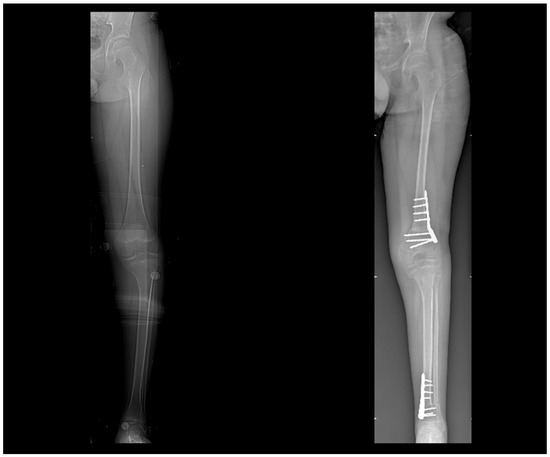

2.2. CT Scan Protocol

3.1. 3D Reconstruction of Patient-Specific CT Scan